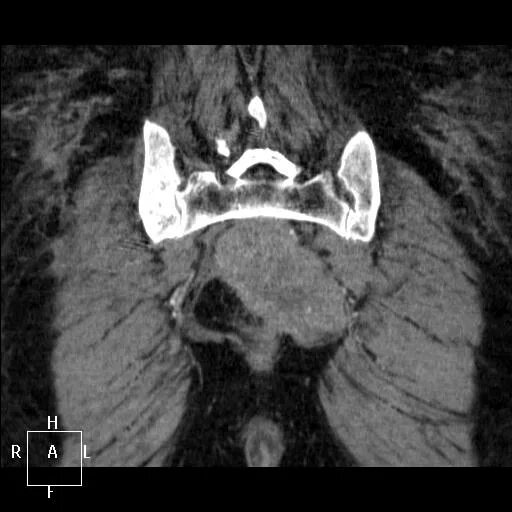

Метастазы в крестце